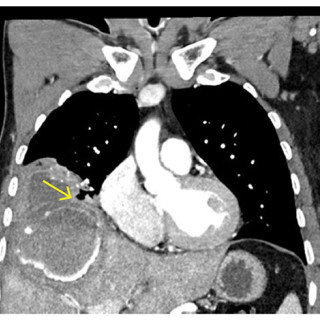

Denne kasuistikken beskriver alvorlig iatrogen botulisme etter behandling med injeksjon av botulinumtoksin ved en privatklinikk i utlandet. En kvinne i 40-årene ble akuttinnlagt i medisinsk avdeling grunnet økende svelgparese, svakhet i nakkemuskulatur, obstipasjon, munntørrhet, hodepine, fatigue, tunge øyelokk og uklart syn de siste fem dager. De siste tre dagene før innleggelsen hadde hun ikke fått i seg flytende eller fast føde, og hodet måtte støttes når hun skulle sette seg opp. Det fremkom at hun 15 dager tidligere hadde fått injisert botulinumtoksin type A mot migreneplager under et...